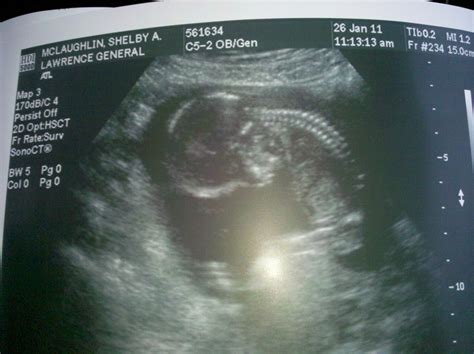

Interpreting the 15 Week Sonogram Results

After the 15 week sonogram, the healthcare provider will review the images and discuss the findings with you. Key points to look for include:

• Fetal Measurements: The baby’s measurements, including the head circumference, abdominal circumference, and femur length, will be recorded to ensure the baby is growing at a normal rate.

• Anatomical Structures: The scan will check for the presence and proper development of all major organs and structures, such as the heart, brain, kidneys, and spine.

• Placental Position: The position of the placenta will be assessed to ensure it is not covering the cervix, which could lead to complications later in the pregnancy.

• Amniotic Fluid Levels: The amount of amniotic fluid will be measured to ensure it is within normal ranges, as too much or too little fluid can indicate potential issues.